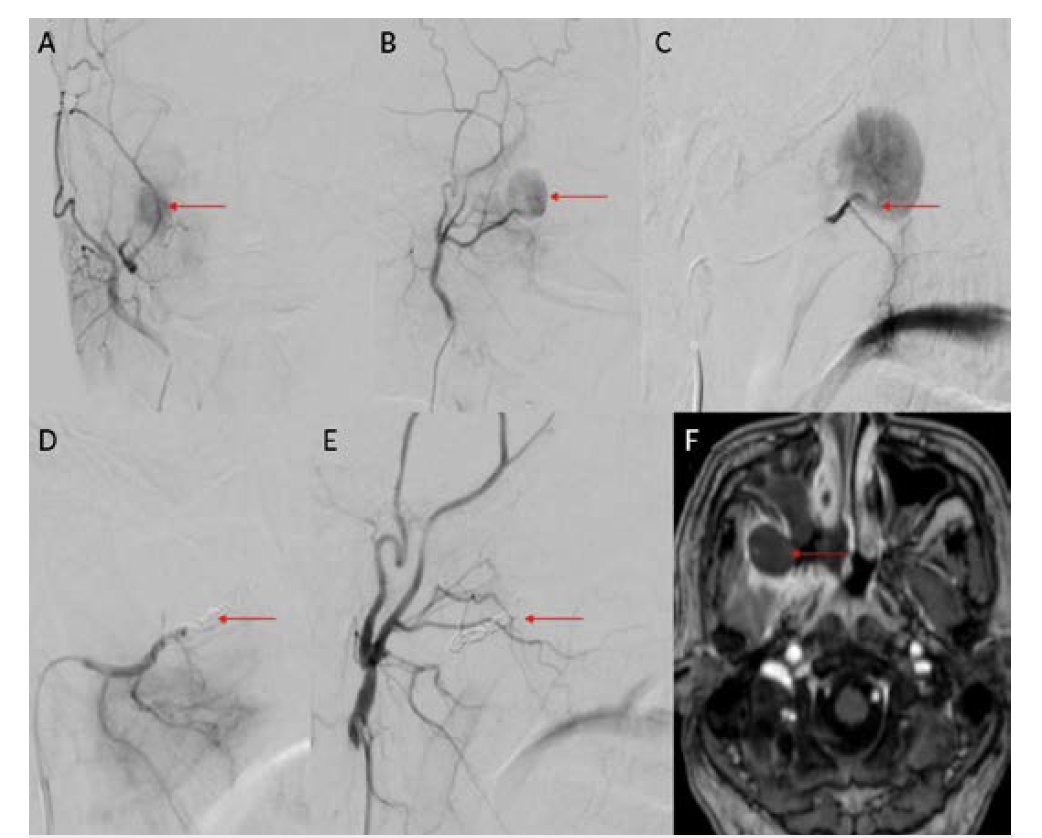

Eight patients were included during this study period; all were men between ages 34 and 61 (Table 1). Positivity to COVID-19 RTPCR test was detected over a period of 2 to 6 months prior to the acute hemorrhage. Six patients presented with massive hemoptysis; 2 presented with severe epistaxis. A contrast-enhanced computed tomography angiography was done in all patients. All 6 patients who presented with massive hemoptysis were detected to have pulmonary arterial pseudoaneurysms with associated cavitary lesions in the lungs (Figure 2). Among the 2 patients who presented with nasal bleed, 1 had a biopsy and culture-proven invasive fungal sinusitis with an internal maxillary artery pseudoaneurysm, probably of mycotic etiology. The second patient also diagnosed with invasive fungal sinusitis had multiple sinonasal debridements outside before presenting with massive epistaxis wherein a diagnosis of internal carotid artery pseudoaneurysm was made, probably secondary to iatrogenic or mycotic etiology. The presence of concomitant COVID-19 infection in these patients predisposed them to impairment of cell-mediated immunity, immune dysregulation, and a decrease in CD4 and CD8 counts, increasing their vulnerability to fungal infections. In 6 patients it was possible to obtain samples for fungal elements through biopsy. Endovascular embolization was performed under local anesthesia in 7 patients, and under general anesthesia in 1 patient. Different embolic agents were used: coils (Figures 3A and 3B), Amplatzer vascular plug (Abbott) (Figures 4A and 4B, Figures 5A and 5B), and glue (Figures 6A and 6B). However, 2 patients underwent lobectomy for extensive parenchymal disease apart from pseudoaneurysm. One patient with pulmonary artery pseudoaneurysm had contrast extravasation into the cavity during the procedure. All patients had cessation of hemorrhage. However, 2 patients required pulmonary lobectomy because of extensive parenchymal disease after embolization for the pseudoaneurysm.

COVID-19 infection has affected people worldwide since 2020 after its initial outbreak in Wuhan, China. It has caused significant mortality and morbidity, causing millions of deaths to date. COVID-19 infection is known to affect multiple organs such as the lungs, heart, brain, and skin, with the lung being most common.1 Patients with COVID-19 usually present with complaints of fever, cough, malaise, and difficulty breathing.1 Diabetes mellitus is an independent risk factor for COVID-19 infection.1 Fungal infection was a known complication following COVID-19 infection, especially in those with poorly controlled blood sugar and who have been treated with immunosuppressive agents such as steroids.2,3 Pulmonary complications following COVID-19 infection were mainly related to fibro-cavitary changes.3-5 Hemorrhage following fungal infection was mainly due to vascular involvement and formation of pseudoaneurysm.6 Patients with severe COVID-19 infection may have endothelial inflammation and secondary fungal infection, leading to pseudoaneurysm formation with a risk of increased bleeding.5,6 Fungal sinusitis following COVID-19 infection is a well-known entity that can cause bleeding due to the involvement of the internal and external carotid vessels.2,3,5 Extracranial carotid artery aneurysms are found most frequently in the common carotid artery at or near the bifurcation, less frequently in the internal carotid artery (Figures 7A and 7B), and least often in the external carotid artery.7,8 Ongoing studies of the precise molecular underpinnings of mycotic pseudoaneurysms suggest that arterial wall breakdown is likely caused by matrix-degrading enzymes produced by either seeded bacteria or inflammatory cells of the host response.6 Diabetes and fungal infections are more frequently documented, which could result in mycotic aneurysm, spontaneous rupture, and massive hemorrhage.2,3,5

Pulmonary artery pseudoaneurysm is a rare but important entity because of its high risk of life-threatening hemorrhage.2,5,9,10 Peripheral branches of the lower lobe pulmonary artery are most commonly affected.2,5,10 A pseudoaneurysm is different from a true aneurysm because there is no wall except for the hematoma that is surrounding and containing it.6,9,11,12 The etiology of a pulmonary artery pseudoaneurysm is inflammatory erosion secondary to tuberculosis (Rasmussen aneurysm), necrotizing pneumonia, bacterial endocarditis, mucormycosis, or vasculitides (Marfan syndrome, Behçet’s disease, etc.). Other causes include necrotic cavitary lung carcinoma, congenital heart disease, and traumatic injury. Iatrogenic pseudoaneurysm secondary to pulmonary artery catheter placement has also been reported.4-6,9-11 Internal maxillary artery pseudoaneurysm is rare and is more commonly encountered following trauma and iatrogenic injury (Figures 8A and 8B).7,8,13 These patients present with massive or moderate bleeds, which can lead to death in about 50% of cases if left untreated.2,4 The most common artery leading to hemoptysis is the bronchial artery, which constitutes around 80% to 90%.4,5,13 Hemoptysis related to the pulmonary artery constitutes around 10%.10,14 Multidetector computed tomography (MDCT) pulmonary angiography is the modality of choice to diagnose pulmonary artery aneurysms.2,9,10,12 It provides detailed information about the presence, number, size, shape, and origin of pulmonary artery aneurysms.2,9,10 MDCT also allows detailed assessment of the orientation and size of the aneurysmal sac and size of the neck on multiplanar reconstruction.2,10 It also gives an overall idea about the pathology, and the involved lung segment eventually helps in planning the treatment accordingly.4,10,12,14 Digital subtraction angiography has the advantage of allowing endovascular intervention at the time of diagnosis.4,12,14 Ultrasound and magnetic resonance imaging are also used in cases of aneurysms involving neck vasculature.2,14,12